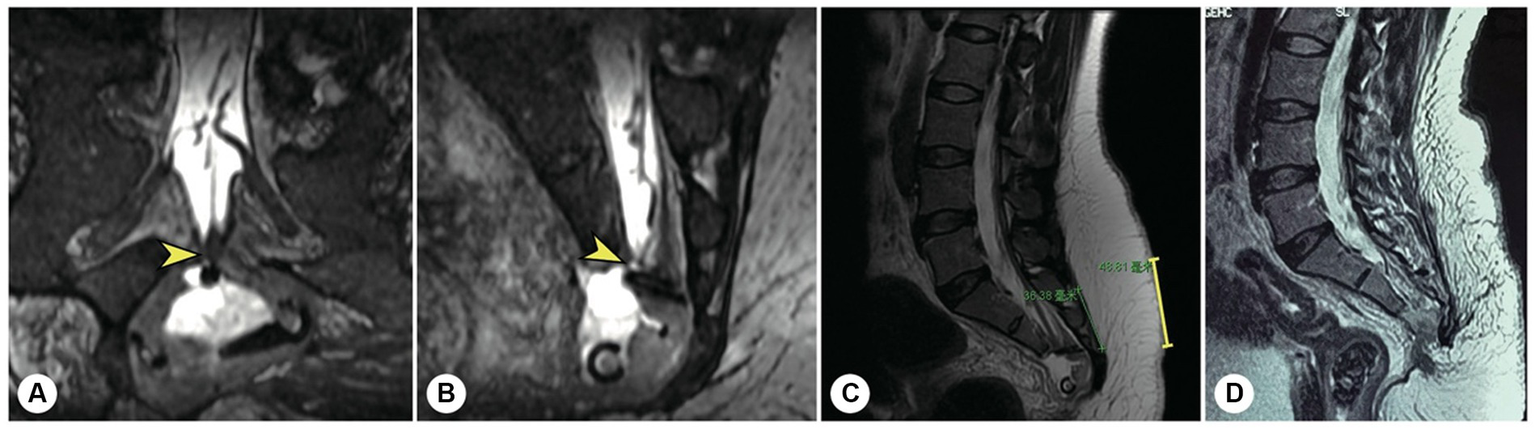

Figure 7

The other representative patient had both sacroanterior and sacral cysts. A 45 years-old female presenting with abdominal pain was found to have a pelvic mass on CT at the local hospital. The intrapelvic part of the cyst was resected under laparoscopy. (A) After referral to our institute, coronal reconstructed MR image showed a narrow-neck leakage orificium (yellow arrowhead) between the end of the dural sac and the sacral canal cyst, and the filum terminale was thickened. (B) Sagittal reconstructed MR image showing the leakage orificium (yellow arrowhead) at the end of the dural sac connected to the sacral cyst and the residual sac. (C) A 4 cm precise incision was made (yellow line segment). (D) After the leakage orificium was ligated and the tethered spinal cord was released, a follow-up MRI showed that the cyst had completely vanished.